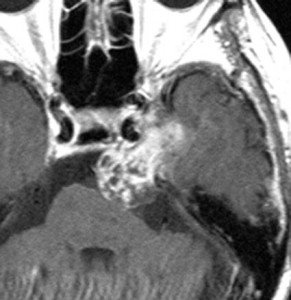

開頭手術で摘出した方がよい三叉神経鞘腫

この腫瘍もちょっと大きいので放射線治療だけで治すことは難しいでしょう。この三叉神経鞘腫は少し大きいかなと思うくらいの大きさです。 脳幹部が圧迫されていますから手術摘出した方がいい例です。これも側頭部の前の方の骨を開頭するだけで全部取れます。